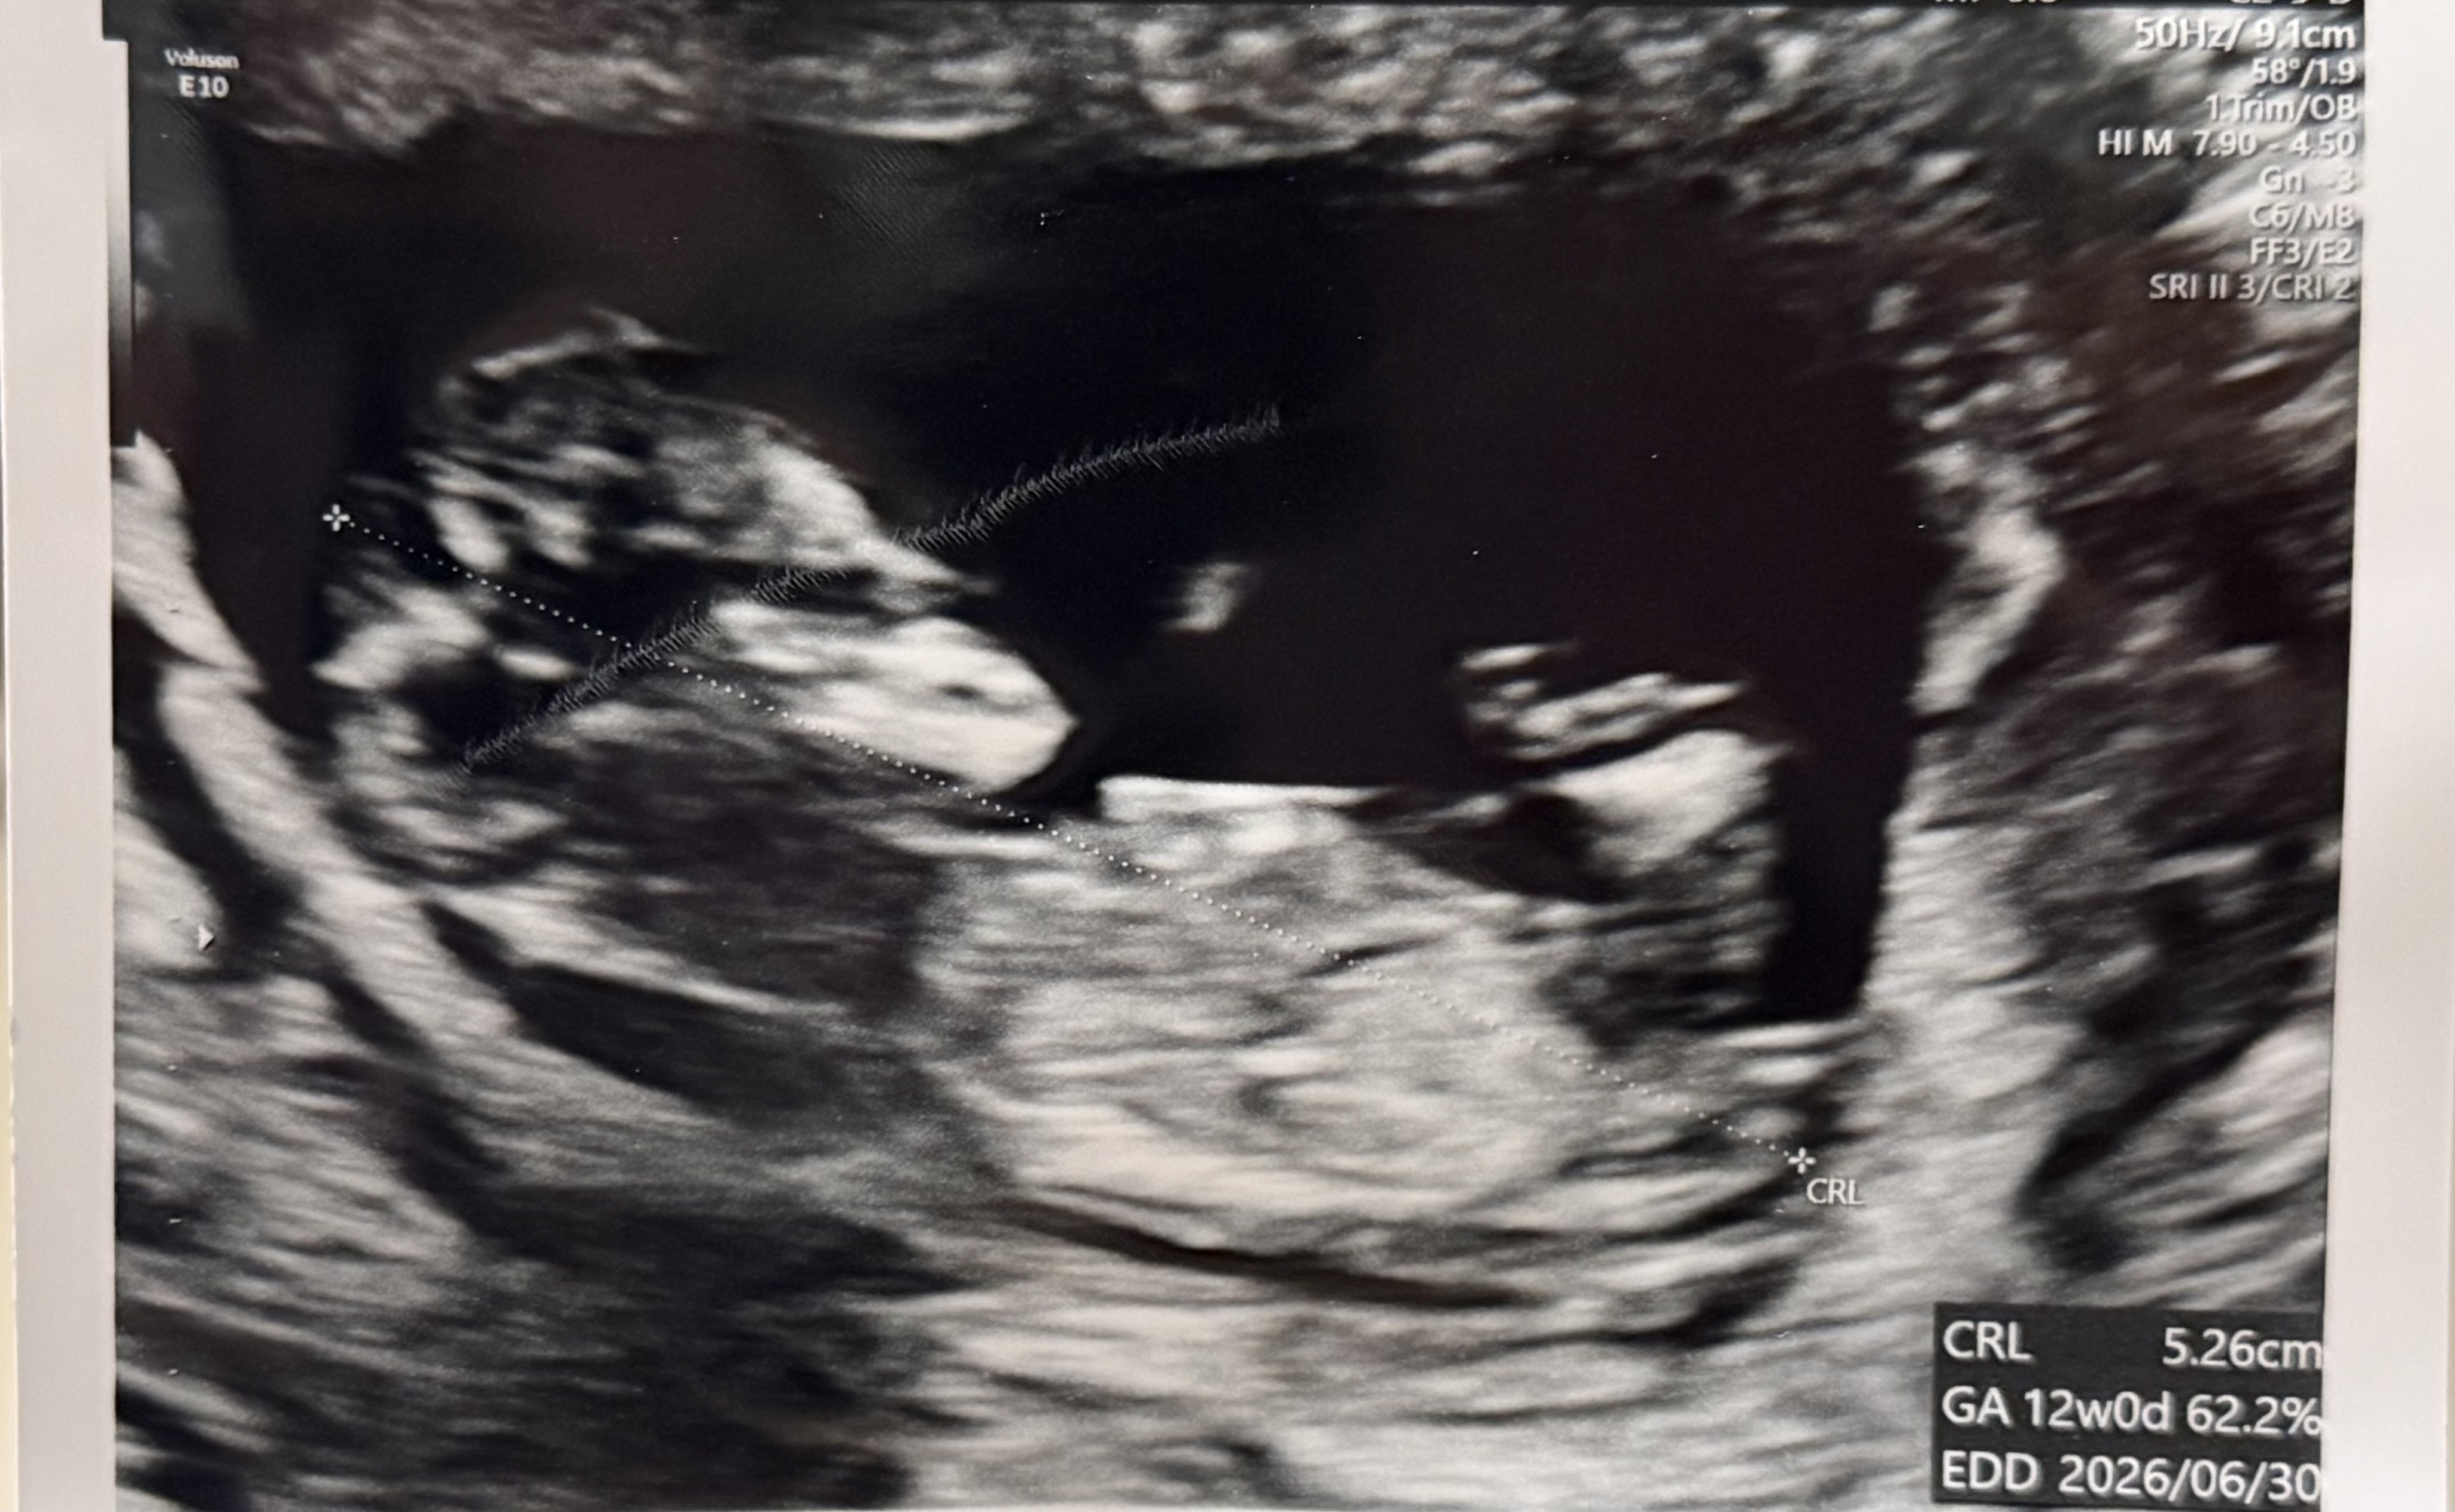

11주4일 옆모습 춈파에요!!이정도면?

오늘 목투명대 검사하고 0.8 나왔고 옆태 보고왔는데 각도법 지금도 볼수있나요?